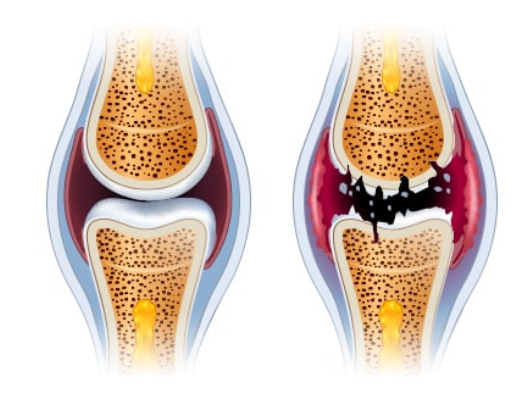

글루코사민은 우리 몸의 연골을 이루는 필수성분으로 관절에 탄력성을 주고, 관절 강도를 높이는 역할을 합니다.

연골의 필수 성분인 글루코사민은 우리 몸에서 원래 스스로 생성되는 성분입니다. 그러나 나이가 들어 가면서 글루코사민 생성 능력은 현저히 감소하게 됩니다. 이에 따라 자연스럽게 관절연골의 완충 능력은 나빠지게 되고, 손상받기 쉬운 상태가 되어 버립니다. 그리고 이 손상이 염증을 유발합니다. 이것이 바로 관절염입니다.

줄어든 글루코사민 생성능력만큼 음식이나 영양제를 통해 글루코사민을 충분히 공급해주면면 연골의 파괴를 막을 수 있고, 연골 세포의 증식을 촉진시킬 수 있습니다. 그러므로, 적절한 글로코사민 섭취는 관절염 등 관절 질환을 앓고 있는 사람들에게 큰 도움을 줄 수 있습니다.